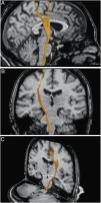

ResultadosSe demostraron y describieron anatómicamente el tracto corticoespinal y lemnisco medial en gran parte de sus trayectorias, identificando las relaciones entre sí y con otros haces de sustancia blanca y núcleos de sustancia gris cercanos, especialmente en el troncoencéfalo, con la correspondiente representación mediante DTT.

ResultsThe main bundles of the cortico-spinal tract and medial lemniscus were demonstrated and delineated throughout most of their trajectories, noticing their gross anatomical relation to one another and with other white matter tracts and gray matter nuclei the surround them, specially in the brain-stem; together with their corresponding representation on DTT images.